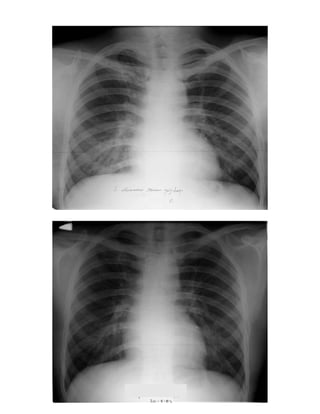

12. Περίπωση επαφής 574